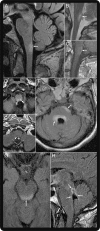

Neuromyelitis optica (NMO) is an inflammatory CNS syndrome distinct from multiple sclerosis (MS) that is associated with serum aquaporin-4 immunoglobulin G antibodies (AQP4-IgG). Prior NMO diagnostic criteria required optic nerve and spinal cord involvement but more restricted or more extensive CNS involvement may occur. The International Panel for NMO Diagnosis (IPND) was convened to develop revised diagnostic criteria using systematic literature reviews and electronic surveys to facilitate consensus. The new nomenclature defines the unifying term NMO spectrum disorders (NMOSD), which is stratified further by serologic testing (NMOSD with or without AQP4-IgG). The core clinical characteristics required for patients with NMOSD with AQP4-IgG include clinical syndromes or MRI findings related to optic nerve, spinal cord, area postrema, other brainstem, diencephalic, or cerebral presentations. More stringent clinical criteria, with additional neuroimaging findings, are required for diagnosis of NMOSD without AQP4-IgG or when serologic testing is unavailable. The IPND also proposed validation strategies and achieved consensus on pediatric NMOSD diagnosis and the concepts of monophasic NMOSD and opticospinal MS.